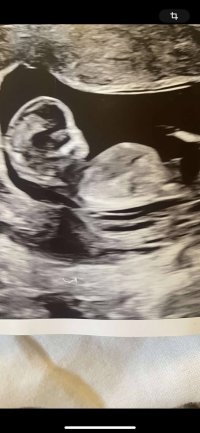

Noen som har hatt samme nub på ultralyd og fått jente? Vi har en gutt her hjemme som ønsker seg så mye en lillesøster han kan kalle opp etter oldemor. Vi blir selvfølgelig like glade for en gutt til dette er uke 13+2